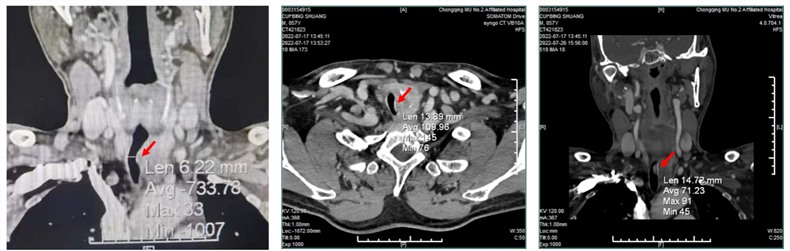

57岁的患者曹先生(化名)是身强力壮的务工人员,近期反复咳嗽,且偶伴痰中带血。曹先生并不以为意,觉得拖一拖也许就好了,在家人的多番催促下才到医院检查。“不查不知道,一查吓一跳”,当地医生告诉他初步诊断